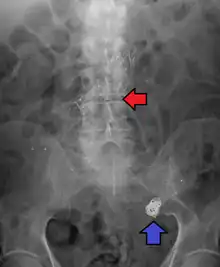

Abdominal aortic aneurysms are commonly divided according to their size and symptomatology. An aneurysm is usually defined as an outer aortic diameter over 3 cm (normal diameter of the aorta is around 2 cm),[37] or more than 50% of normal diameter that of a healthy individual of the same sex and age.[10][38] If the outer diameter exceeds 5.5 cm, the aneurysm is considered to be large.[36]